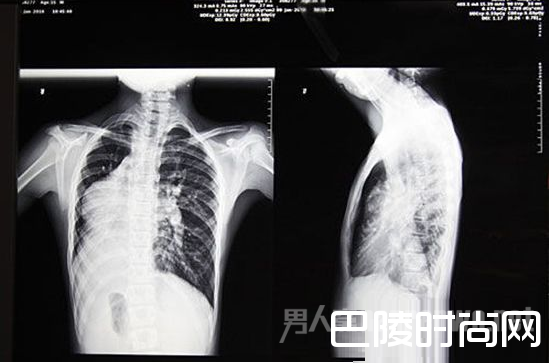

本来一个简简单单的手术,却因为“镜面人”的关系让主刀医生们都苦不堪言。相信很多人也都在疑问,镜面人是什么?男子五脏六腑颠倒又是怎么一回事呢?接下来小编就要为大家介绍介绍这个神奇的“镜面人”。

体内的脏器类似于正常人照镜子,五脏六腑的位置与常人相反,过着“颠倒”的人生,这就是我常说的“镜面人”,发生概率只有百万分之一。

X光片

得知需要手术,张先生脱口而出的第一句话就是:“我是个镜面人。”这意味着,他的心、肝、脾等脏器都在与常人相反的位置,肠道也是如此。“一般人的大肠是顺时针的,阑尾在右侧,而镜面人的大肠是逆时针方向,阑尾在左侧。”

上学体检去拍X片

医生却以为他在恶作剧

上小学的那年需要体检,去拍X光片的时候,医生却特意喊他“不要背对着机器,脸朝向医生”,“其实他哪里知道,我当时就是脸朝着他的,他却以为我在开玩笑恶作剧。”